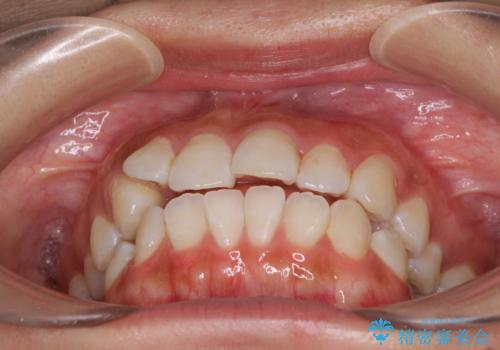

前歯のデコボコが気になる インビザラインによる矯正治療

- 上下前歯のデコボコを気にして来院された患者様です。

インビザラインによる上下歯列の拡大と、IPR(歯と歯の間を削る)にるスペースの獲得により、前歯のデコボコを改善することとしました。